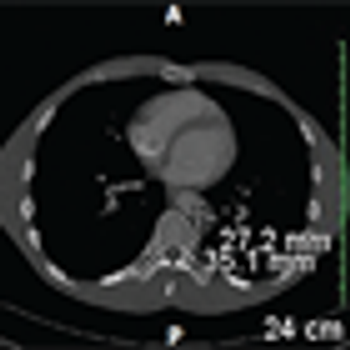

A Rare Case of Metastatic Renal Epithelioid Angiomyolipoma

ByElaine T. Lam, MD,Francisco G. La Rosa, MD,Thomas D. Suby-long, MD,Kimi L. Kondo, DO,Shandra S. Wilson, MD,L. Michael Glodé, MD, FACP,Thomas W. Flaig, MD The patient is a 43-year-old man who was initially evaluated at an outside institution for unexplained anemia and who was found to have a large right kidney mass. He underwent a radical nephrectomy for a 19-cm large-cell, poorly differentiated neoplasm, consistent with pleomorphic, epithelioid angiomyolipoma (EAML) with extensive necrosis and cytologic atypia.